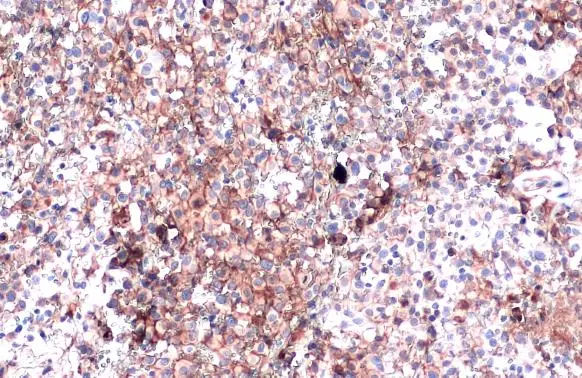

PD-L1 antibody detects PD-L1 protein at cell membrane in PD-L1 protein-expressing cell lines by immunohistochemical analysis.  Antibodies: PD-L1 antibody (GTX104763) diluted at 1:1000, and competitor's antibody diluted at 1:50. Samples:  Negative (-), low positive (+), intermediate positive (++) and strong positive (+++) cell line cores assessed using Quantitative Digital Pathology.

Antigen Retrieval: Citrate buffer, pH 6.0, 15 min